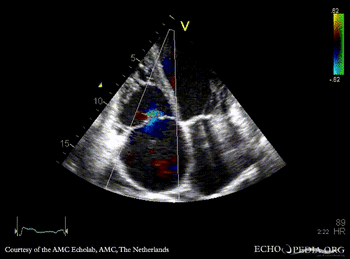

A4CH: prolaps of PMVL, enlarged left and right atrium, poor function of dilated right ventricle A4CH: Color doppler, severe mitral regurgitation